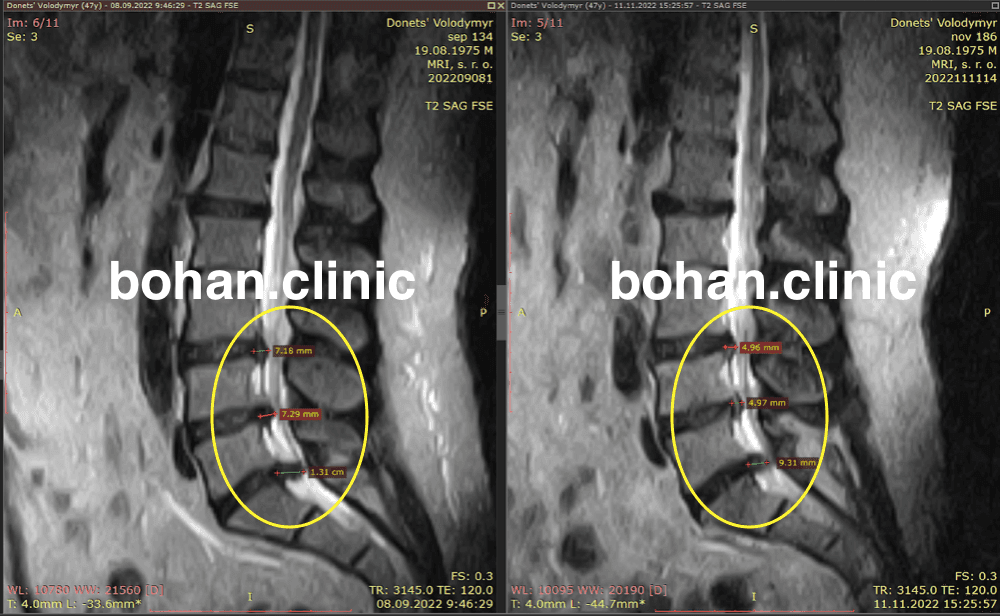

Метод лікування грижі шляхом стимуляції резорбції в Україні був впроваджений у 2020-2021 роках.  Алгоритм оцінки грижі на предмет резорбції, що використовується у клініках – є авторським, розроблений лікарем Боханом А.Ю.